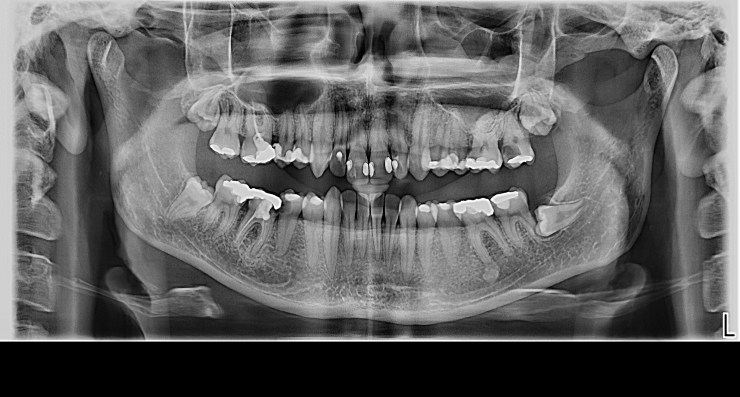

Digitalna ortopan snimka

Ortopantomogram (skraćeno ortopan) snimanje predstavlja 2D rentgensku snimku svih zubi gornje i donje vilice s okolnim anatomskim strukturama. Intraoralna dentalna slika daje prikaz pojedinačnog zuba, detalje krune i korijena te okolnih struktura parodonta i alveolarne kosti.

Digitalni ortopan označava korištenje najsuvremenije digitalne tehnologije prilikom snimanja.